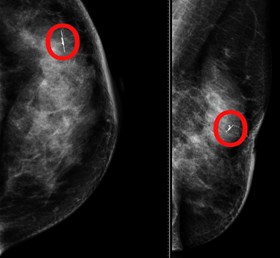

Senologia, “radar” individua lesioni tumorali impalpabili

L'innovativa metodica guida i chirurghi in sala operatoria e permette di avere una cicatrice meno evidente